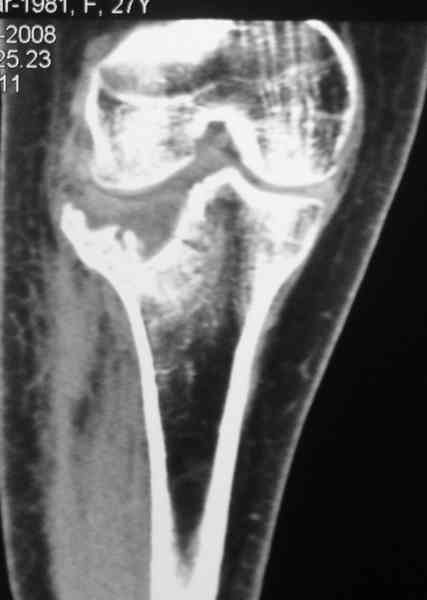

По тактике лечения, более импонирует второй вариант, но наружная плато расколота и туда при нагрузке внедряется н/мышелка бедра, поэтому после дистракции как репонирвать: или стяжными винтами, или изогнутами спицами или субхондральная костная пластика?

Уважаемый Абдурашид. Если нет противопоказаний , то из оперативных способов, я бы рекомендовал следующие: Полное замещение наружного мыщелка аллотрансплантатом либо открытая репозиция с элевацией и замещение дефекта ауто или аллокостью. В Ваших условиях , я бы рекомендовал второй способ. Во-время элевации необходимо разъединить фрагменты со стороны сустава ( надсечь скальпелем по линиям перелома, а затем тонким остеотомом их разъединить. При помощи долота произвести неполную остеотомию ( захватите не менее 1,5 - 2 см губчатой кости и поднять фрагменты, визуально отрепонировать и фиксировать 2-3 спицами. Дефект заместить костным ауто или аллатрансплантатом. Окончательная стабилизация пластиной ( лучше с угловой стабильностью, либо АВФ - позволит спокойно устранить угловую деформацию.